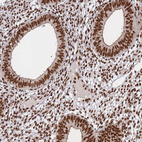

Immunohistochemical staining of human lymph node shows strong nuclear positivity in lymphoid cells.